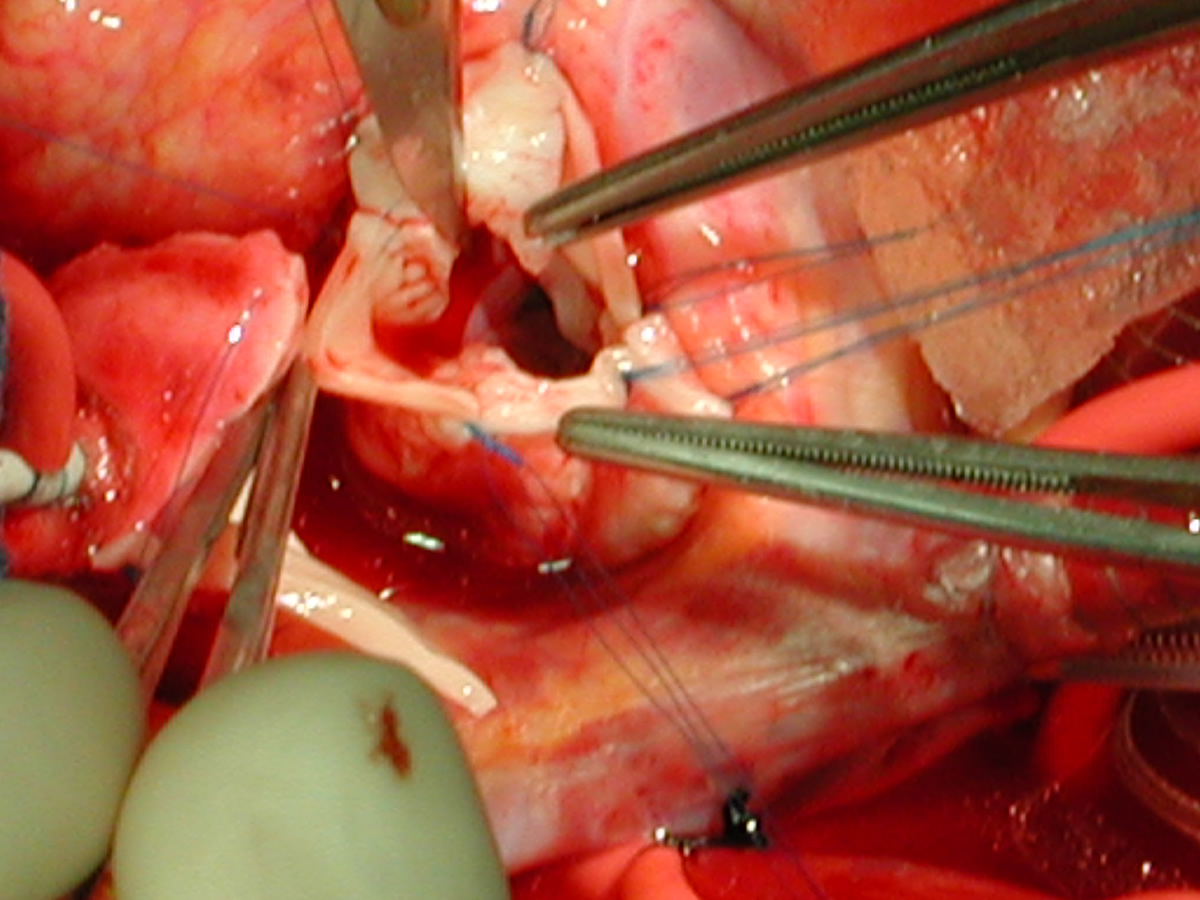

The operative approach is through a median sternotomy with the use of cardiopulmonary bypass and bicaval venous cannulation. The first dose of cold blood cardioplegia is antegrade; the remaining doses are retrograde.

High ascending aortic cannulation adjacent to the innominate artery for maximum exposure of the ascending aorta and to allow length for positioning of the patch in the ascending aorta.

One dose of antegrade cardioplegia followed by retrograde cardioplegia.

Pulmonary homograft or pericardial patches (tanned in glutaraldehyde) for the “shields”. These patches should not be too large – this will lead to aortic insufficiency.

First coronary sinus incision in noncoronary sinus to facilitate exposure of the incisions into the coronary orifice sinuses.

In most cases, the right coronary artery sinus should be opened to the left of the coronary orifice and the left coronary artery sinus to the right of the coronary orifice. Occasionally one may not have enough room between a coronary orifice and the aortic valve; in this case the incision site should be tailored to the situation.

Ensure similar orifice sizes between the proximal and distal ascending aorta after patch augmentation by the use of a sizing dilator.

Transesophageal echocardiography to assess completeness of repair, coronary blood flow postoperatively, wall motion abnormalities, and adequacy of aortic valve.